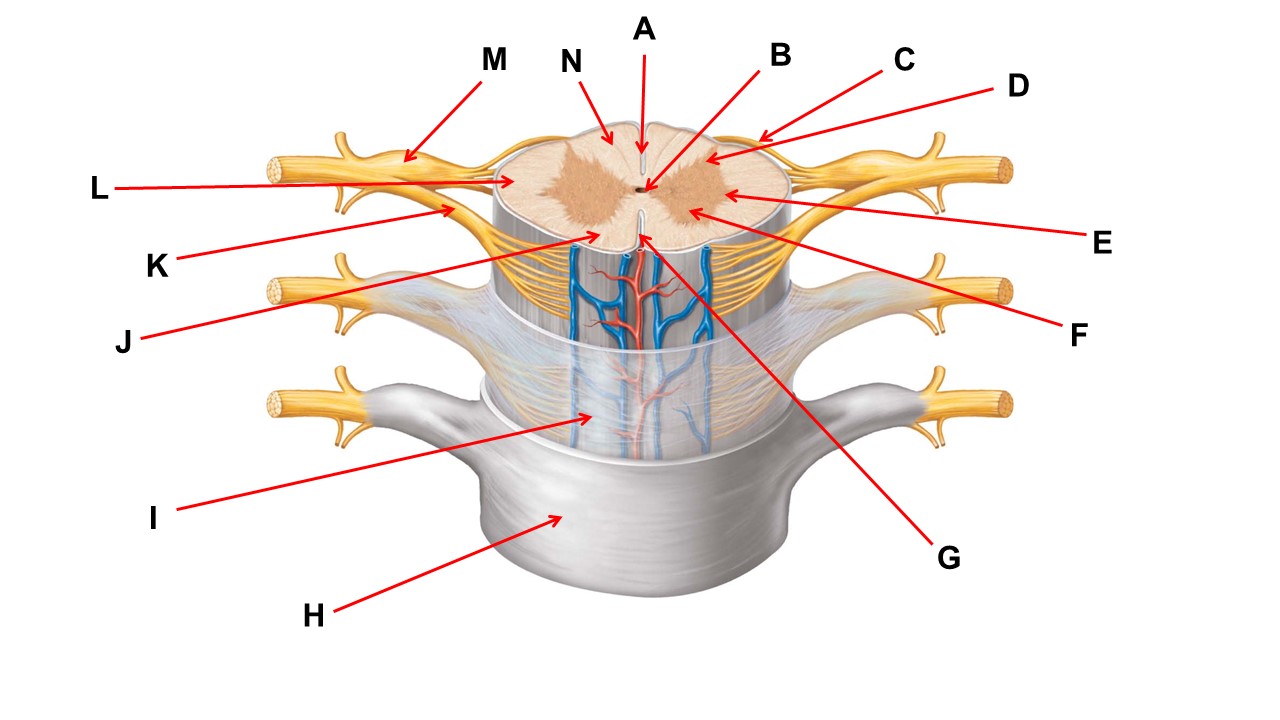

Name the region within bracket D.

Name the region of tissue surrounding the tip of arrow E.

Name the region of tissue surrounding the tip of arrow B.

dorsal horn

Name the structure at the tip of arrow K.

ventral root

Name the region of tissue surrounding the tip of arrow J.

ventral column

Name the region of tissue surrounding the tip of arrow E.

lateral horn

Name the region of tissue surrounding the tip of arrow N.

dorsal column

Name the deep groove at the tip of arrow G.

anterior median fissure

Which structure(s ) would be found in the area at the tip of arrow D.

cell bodies of interneurons

Name the region of tissue surrounding the tip of arrow E.

ventral horn

Name the region within bracket G.

gray commisure